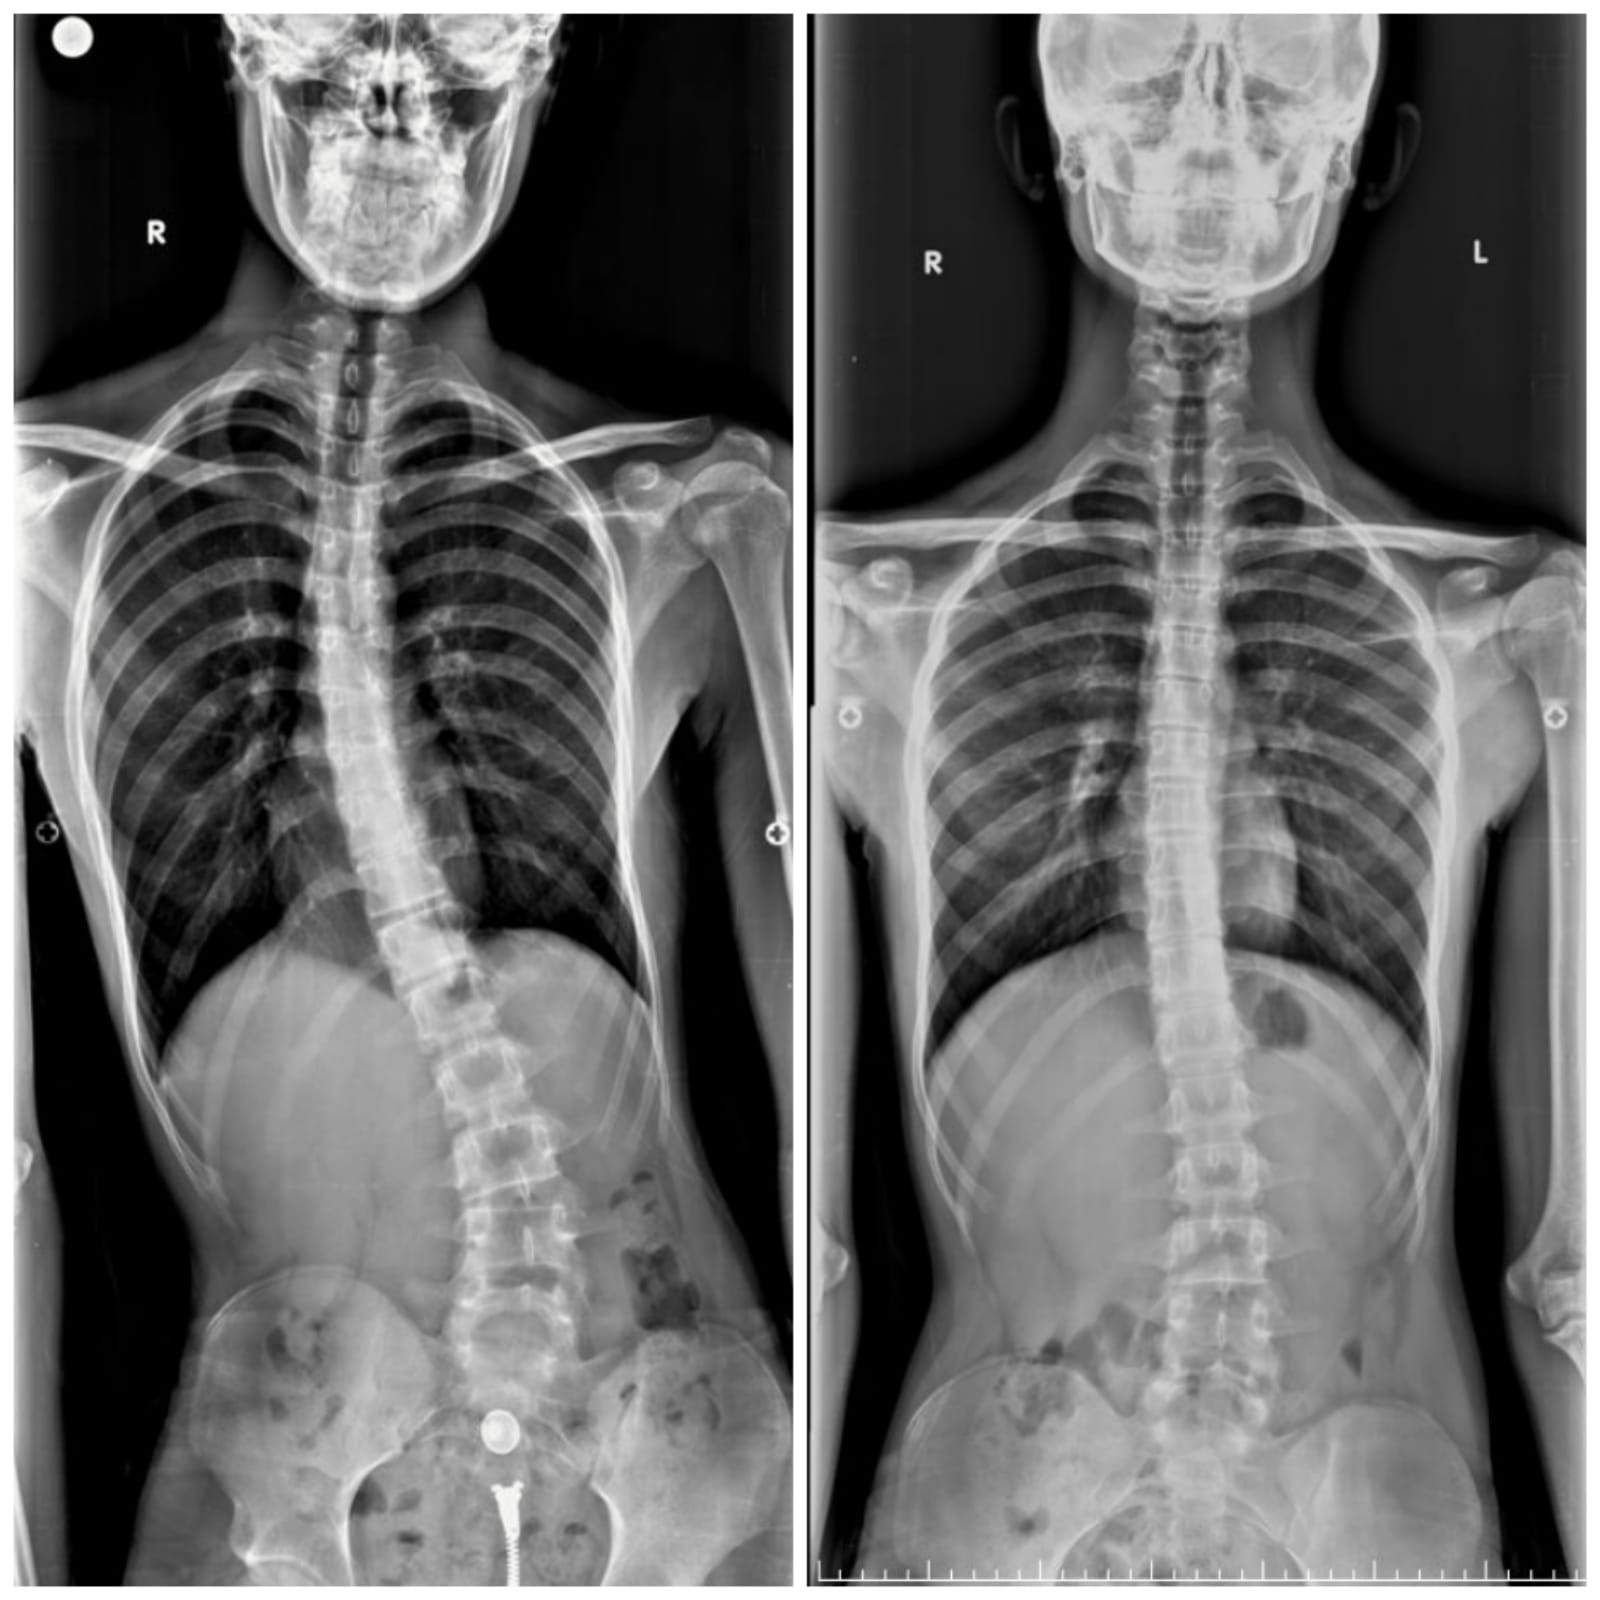

Geçirdiği hafif kaza sonrasında hastaneye gitmeyen Aziz Koray Diş, düştükten sonra vücudunda oluşan yaralara bakmak için aynanın karşısına geçince şok oldu. Vücudundaki eğriliği fark ederek annesine söyleyen ve sonrasında hastane hastane gezen Aziz Koray Diş’e bir türlü doğru teşhis konulamadı. Umudunu kaybetmek üzere olan genç, son olarak Sakarya Eğitim ve Araştırma Hastanesi’nde görev yapan Doç. Dr. Alauddin Kochai’ye başvurdu. Doç. Dr. Alauddin Kochai’nin yaptığı muayene sonrasında tüm tetkikleri yeniden yapılan 16 yaşındaki Aziz Koray Diş’e Osteoid Osteoma ismi verilen kemiğin iyi huylu tümörü teşhisi konuldu. Yapılan ilk tetkiklerin ardından 25 gün boyunca hastanede kalan Aziz Koray Diş, burada ameliyat için hazırlandı. 22’nci gün Doç. Dr. Alauddin Kochai ve ekibi tarafından ameliyata alınan ve omuriliğindeki tümörün alınması için yapılan operasyon sonrası 2 günde ayağa kalkan Aziz Koray Diş, ameliyattan yaklaşık 2 ay sonra tamamen sağlığına kavuştu.

Aziz Koray Diş’in sosyal hayatını da etkileyecek dereceye gelen eğriliğinin tespiti sonrasında hızlıca tedavi sürecine geçildiğini belirten Sakarya Eğitim ve Araştırma Hastanesi Ortopedi ve Travmatoloji Bölümü’nde görevli Doç. Dr. Alauddin Kochai, “Aziz’in bize geldiğinde ciddi bir eğriliği vardı ve bu eğriliğin kaynağı bir türlü bulunamamıştı. Burada gerekli tetkikleri yaparak bu eğriliğin iyi huylu tümör olduğunu belirledik ve buna yönelik yaptığımız cerrahi sonrasında sağlığına kavuştu ve 2 ay içerisinde tamamen sağlığına kavuştu” dedi.

2 ay içerisinde sağlığına kavuşmanın mutluluğunu yaşayan Aziz Koray Diş, “İlk önce ağrılarım olmuştu ama normal bel ağrısı diye pek umursamamıştım. Sonra bisikletle bir kaza geçirdim ve ayna karşısında yaralarıma bakarken vücudumun eğri olduğunu fark ettim. Sonra anneme göstererek durumu anlattım. O şekilde hastane serüvenimiz başladı. Birkaç tane hastane gezdim ve doğru bir teşhis konulamadı. Daha sonra Sakarya Eğitim ve Araştırma Hastanesi’ne geldim ve burada Doç. Dr. Alauddin Kochai beni 25 gün içerisinde tedavimi yapıp yolladı. 2 ay sonra tamamen sağlığıma kavuştum” diye konuştu.

Oğlunun hastalığına yaklaşık 1 buçuk yıldır çare aradıklarını ve hastane hastane gezdiklerini aktaran anne Kadriye Akça ise, “Oğlum için yaklaşık 1 buçuk yıldır çare arıyorduk. Özel hastanelerde gezdik, skolyoz diyerek bir hayli masraf ettirdiler ancak sonuç alamadık ve hastalık daha da fazla ilerledi. Sakarya Eğitim ve Araştırma Hastanesi’ne gelerek burada Doç. Dr. Alauddin Kochai ile görüşerek durumu anlattık. Hemen yatış verdi ve tekrar bütün tahlilleri yaparak teşhisi koydu. Sonra da ameliyat sonrasında çocuğumun ağrıları 2 gün içerisinde geçti. Evimize gittikten sonra daha da iyileşti, şimdi hastalıktan hiçbir eser kalmadı diyebilirim” ifadelerini kullandı.